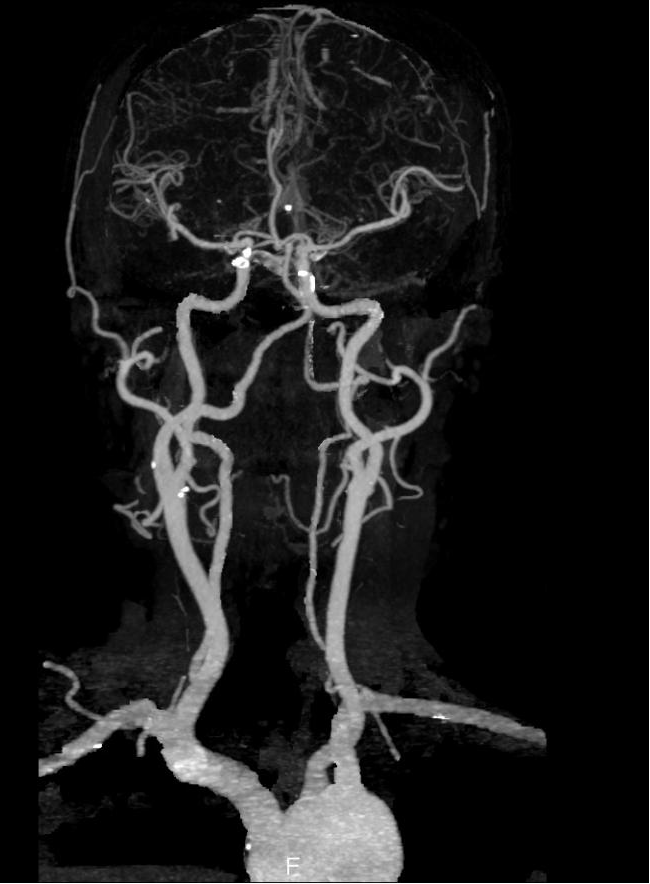

全身各部位血管造影:Incisive CT可以轻松实现大范围CT血管造影(CTA),准确了解血管及相关脏器的形态结构,评估血管及脏器功能,准确判断出血,栓塞、血管瘤、血管畸形、狭窄及肿瘤供血情况,为临床治疗提供极大帮助。

▲ 头颈部CTA、硬化斑块清晰显示